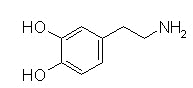

Dopamine and Dobutamine

![]() |

Overview:

Dopamine (Intropin), at low concentrations, acts at D1 receptors and improve myocardial contractility (positive inotropism).

Dopamine (Intropin) produces less of an increase in heart rate compared to isoproterenol (Isuprel) and dopamine (Intropin) dilates renal arteries, promoting better kidney perfusion.

Dobutamine (Dobutrex),

through complex actions mediated by

and ß receptors enhances contractility without

substantially increasing either heart rate or peripheral

resistance.

Dopamine (Intropin) and dobutamine (Dobutrex) are used for short-term inotropic support of the failing heart.

Dobutamine is less arrhythmogenic and produces less tachycardia compared to endogenous catecholamines or isoproterenol (Isuprel).